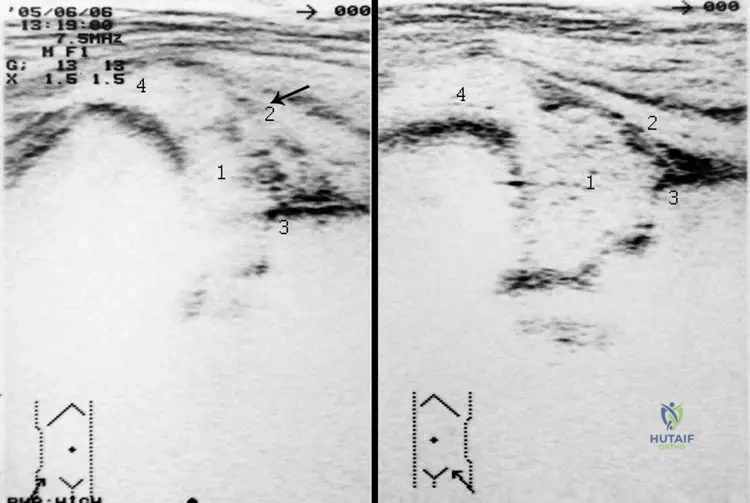

Question 63

A 55-year-old female presents with generalized fatigue. Laboratory workup reveals elevated serum calcium and elevated parathyroid hormone (PTH) levels.

View Answer & Explanation

Correct Answer: C

Rationale: The provided text states that increased PTH consequently leads to increased bone resorption, allowing flow of calcium from bone to blood. This is a primary mechanism by which PTH elevates serum calcium. Option A is incorrect as PTH increases serum calcium. Options B and D are incorrect as PTH reduces renal clearance of calcium and increases intestinal calcium absorption, respectively.

Question 64